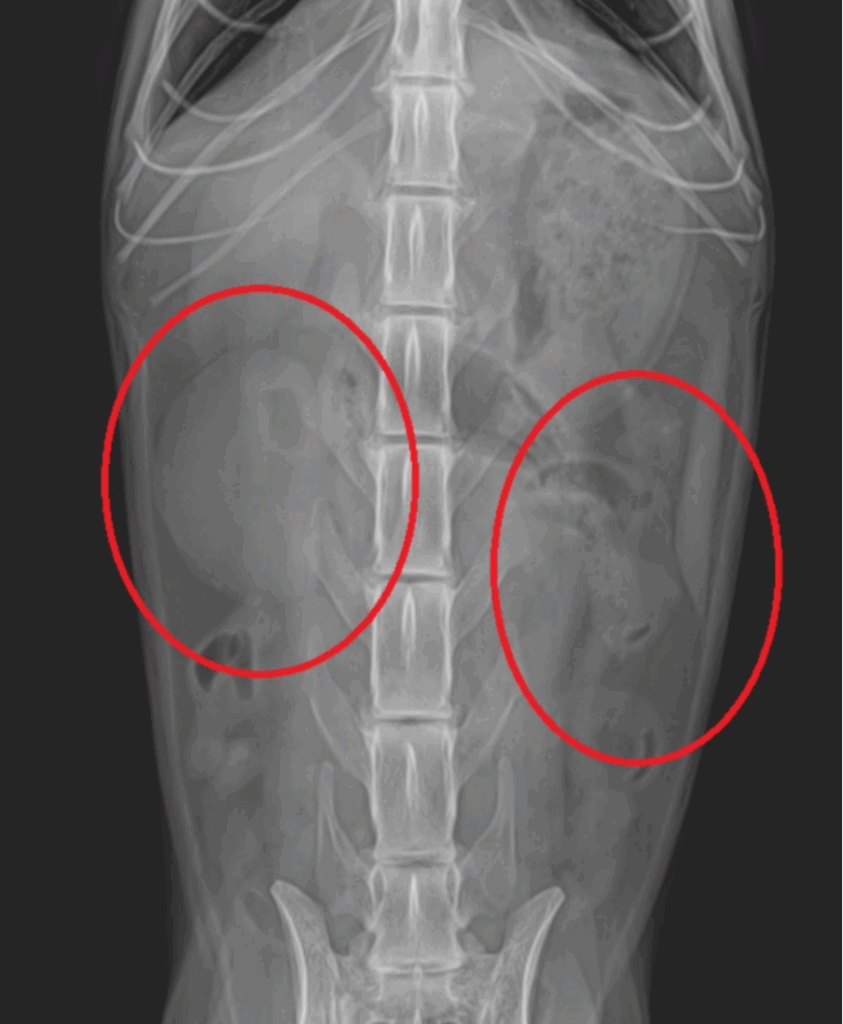

본 환자는 좌측 신장 구조물이 확인되지 않는 선천적 신장 무형성 환자입니다.

우측신장구조물(좌) / 좌측신장구조물 미확인(우) / 출처: 에스동물메디컬센터

양산 에스 고양이 초음파 – 우측신장구조물(좌) / 좌측신장구조물 미확인(우)

즉, 한쪽 신장에 의존해 살아왔으나 나이가 들면서 기능이 급격히 떨어진 상태였던 것입니다.